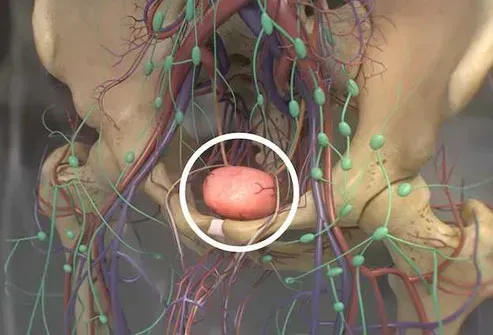

Prostata

Gli uomini hanno una ghiandola di dimensioni noci della prostata che può crescere più grande dopo i 25 anni. Una prostata ingrandita può far sentire il tuo flusso di pipì debole e irregolare. Potresti sentirti come se dovessi andare più a volte. Raramente questo può essere un segno di condizioni più gravi come il cancro. Il medico può aiutare a escludere altre cause e curare la prostata allargata.